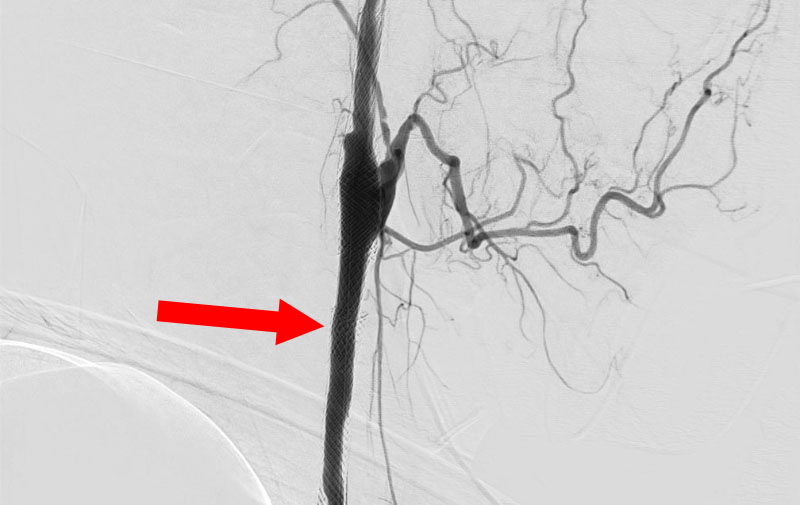

左総頚動脈狭窄症

No.1590 手術前